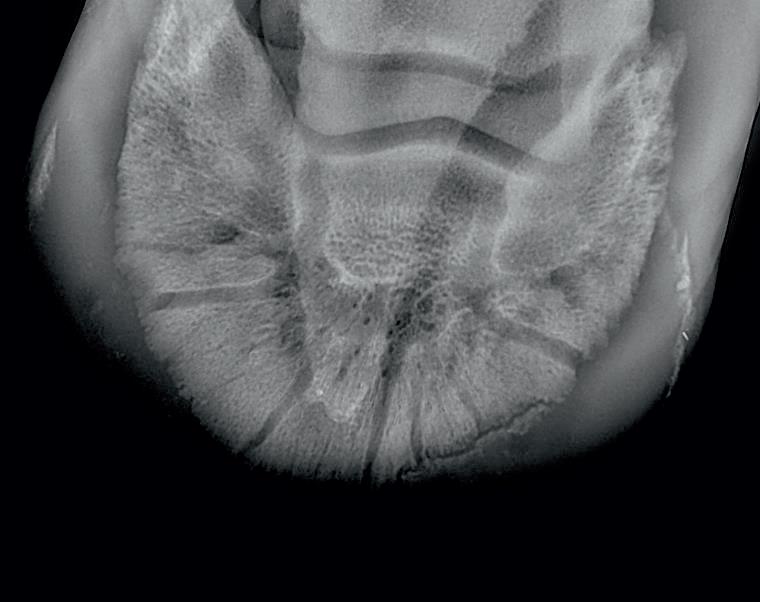

Radiographic proof in clinical results

BONE Gold nutritional bone joint and collagen supplement was formulated to provide some of the essential amino acid requirements of collagen type I, II and III (found in bone and connective tissue) in addition to supporting the nitric oxide pathway which has been found to assist in the formation of bone callus postinjury.

Veterinary surgeons have recommended that Bone Gold may assist with sore shins, tendon injuries, ligament injuries, osteoarthritis and post-surgery in horses and polyarthritis, geriatric osteoarthritis, and post-surgery in dogs.

Here is a veterinary radiographic report on a horse with a fracture evident on the medial toe and after treatment and feeding Bone Gold during this period. More information on these products can be found at www.vetgold.com.au

VETERINARY RADIOGRAPHIC REPORT

HORSE: "XXXXXXXX"

DATES OF EXAMINATION: 26TH AUG, 21ST OCT 21 & 17TH NOV '21

HORSE: “XXXXXXXX”

PLACE: XXXXXXXXXX FARM

DATES OF EXAMINATION: 26TH AUG, 21ST OCT 21 & 17TH NOV ‘21

XXXXXXX's left and right front feet were radiographed on 26th Aug, 21st Oct (8 weeks) and again on the 17th Nov '21(12 weeks).

XXXXXXX’s left and right front feet were radiographed on 26th Aug, 21st Oct (8 weeks) and again on the 17th Nov ‘21(12 weeks).

RADIOGRAPHS:

26.08.21: Right Front: Large P3 solar margin fracture evident on medial toe 32.6mm x 4.1mm with approximately 1.4mm separation from parent bone as below left image.

21.10.21: Right Front: Fine residual 4.2mm fracture still evident, approximately 90% resolution

17.11.21: Right Front: Fracture fully resolved

26TH AUG 21

21ST OCT 21

RECOMMENDATIONS:

Radiographic results as of the 17th Nov '21 show total resolution of the original fracture.

XXXXXXX was reshod today utilising off an alloy shoe with a toe clip - inner circumference seated out to avoid any sole pressure. The horse can return to training.

Please do not hesitate to contact me if you have any further queries

COMMENTS:

Solar margin Type IV fractures of this magnitude have well-documented internationally published healing rates of 7 - 12 months. Full resolution of these fractures is rare as most often the fracture fragments are resorbed. Full resolution in a 3 month period was not anticipated.

The horse was on Bone Gold 3 x scoops fed once per day for this period.

26th August 2021 21st October 2021 17th November 2021